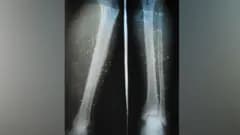

This is the raw, ugly data coming out of the region. It shows exactly how twisted the **regime crackdown** has become. Demonstrators are being shot. The police—ostensibly public servants—are firing birdshot at crowds. We are talking about dozens of lead pellets spraying out to tear up skin and lodge in muscle. It is messy, painful, and incriminating.

In a functional society, a gunshot wound warrants an ambulance. In Iran, calling an ambulance is synonymous with turning yourself in to the secret police. The state has attempted to weaponize the healthcare system, turning doctors into informants. They monitor emergency rooms for **protesters avoiding arrest**. If you have pellets in your leg, you aren't a patient; you are an enemy of the state.